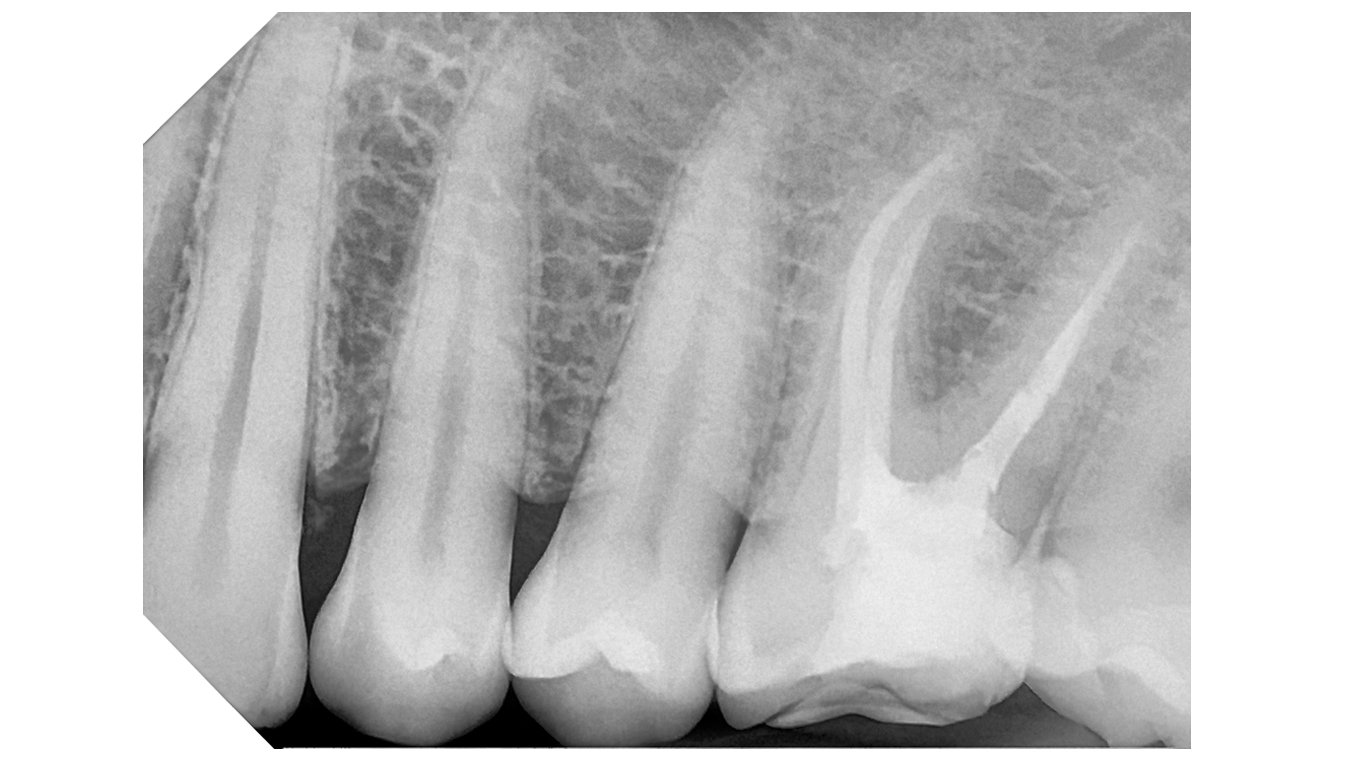

Integrated with the supplied software, the system offers advanced analysis tools and a selection of specific filters to improve image readability in line with clinical requirements:

Default:

High Contrast

High Details

Soft Tissue Preserving

Caries Revealing